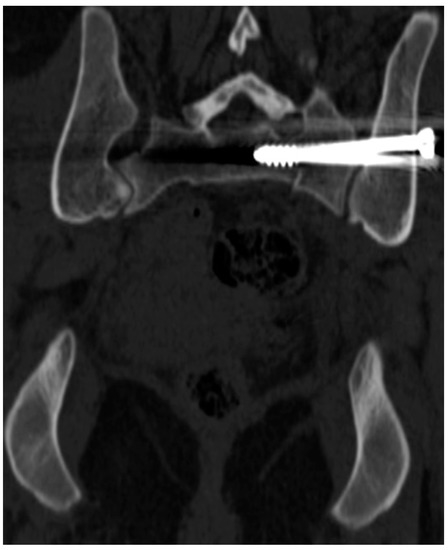

3.2. Number, Localization, and Correct Position of Fixation Screws